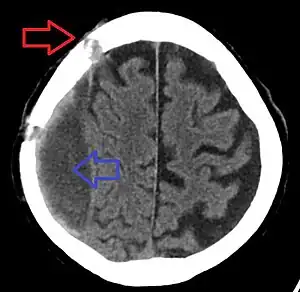

| Chronic subdural bleed with old burr holes | |